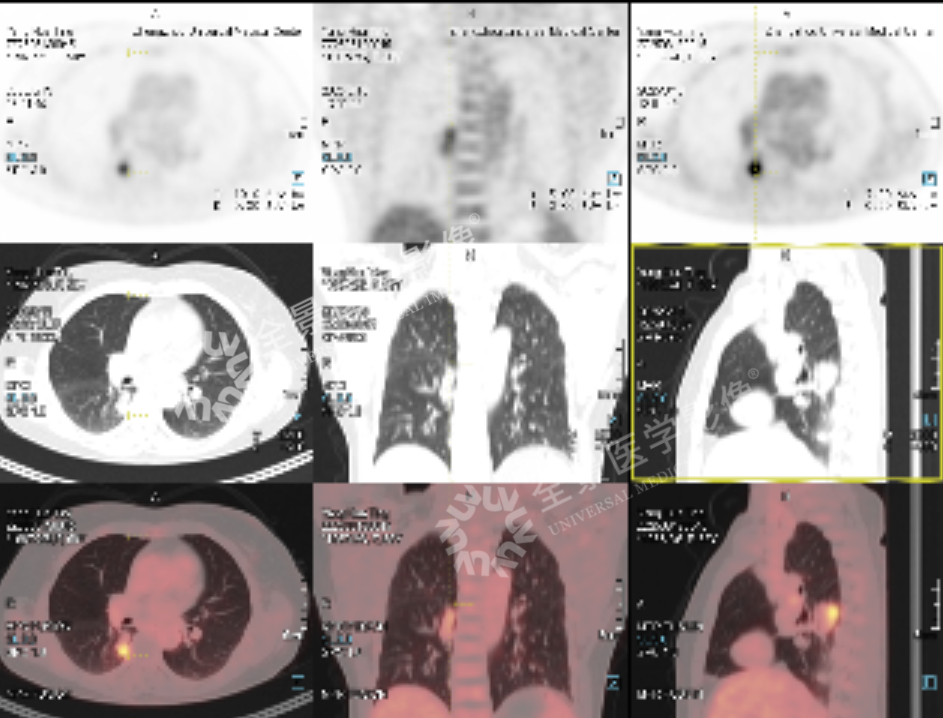

右肺下叶内基底段部分实性结节,部分区域代谢增高,考虑肺原发恶性肿瘤

影像学检查的重要性:本案例中,胸部 CT 和 PET-CT 检查为诊断肺部结节提供了重要信息。CT 检查通过形态、密度、边界和强化特征,初步提示结节的恶性可能性;PET-CT 通过代谢特征进一步支持了恶性肿瘤的诊断。两者结合,提高了诊断的准确性。